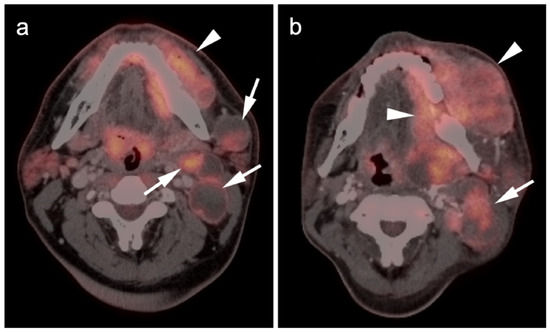

2.3.3. Mucosal Melanoma

2.4. Merkel Cell Carcinoma

- Goerres, G.W.; Stoeckli, S.J.; Von Schulthess, G.K.; Steinert, H.C. FDG PET for Mucosal Malignant Melanoma of the Head and Neck. Laryngoscope 2002, 112, 381–385. [Google Scholar] [CrossRef]